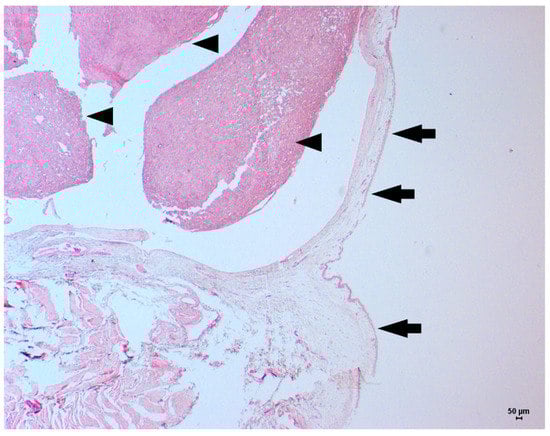

2. Case Description